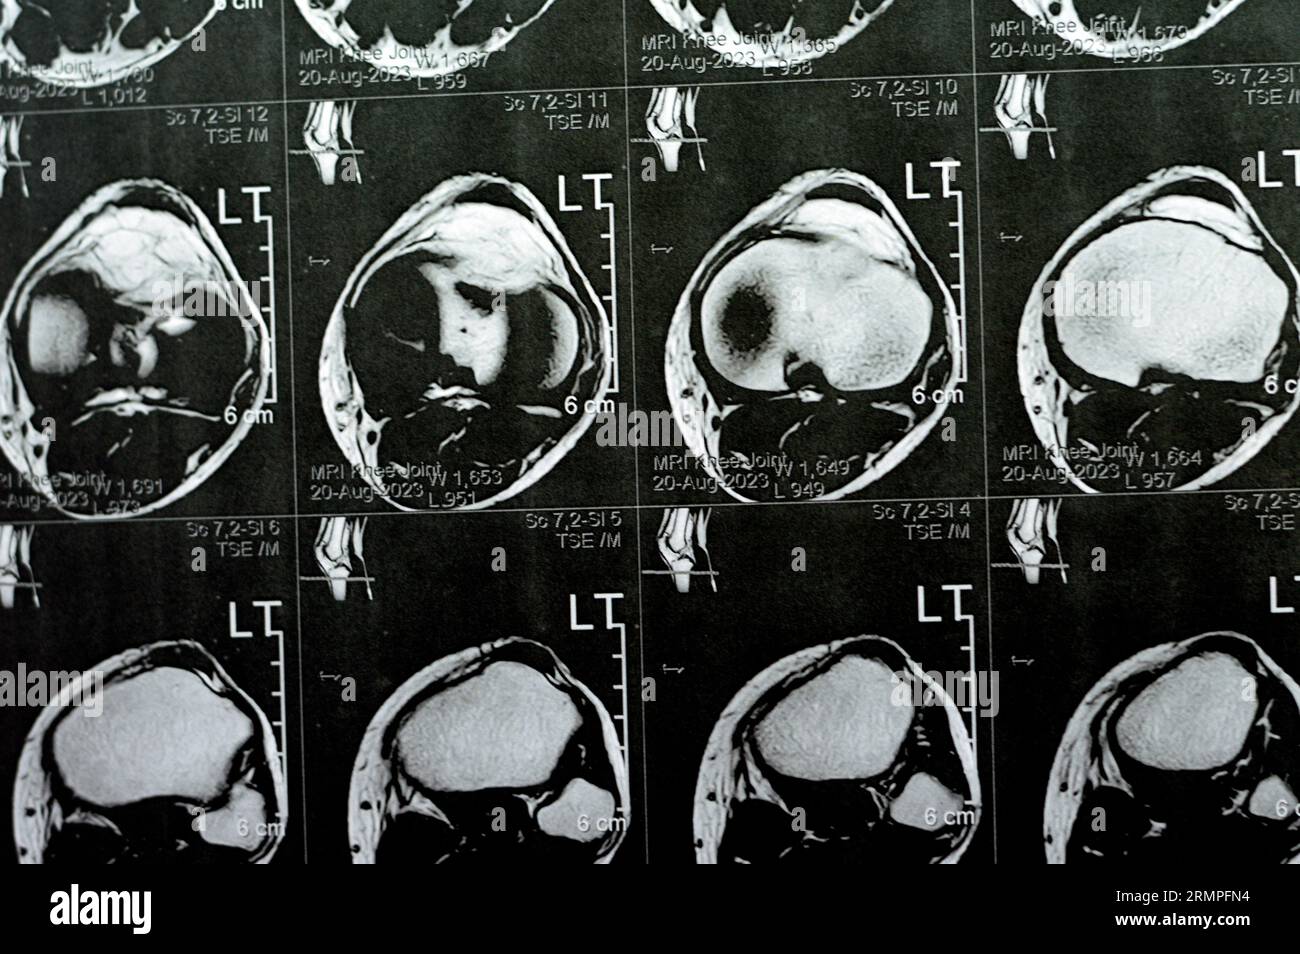

MRI of left knee joint showing minimal joint effusion, PHMM Posterior Anterior Horn Disease Mri Incomplete spinal cord syndromes are reviewed, with descriptions of the relevant spinal cord anatomy and common causes of these syndromes and with emphasis on the correlation of anatomic and imaging findings with clinical manifestations. Emg/ncs, serum and urine electrophoresis,. Diagnostic testing for suspected motor neuron disease should include the following: Amyotrophic lateral sclerosis is a relentlessly progressive neurological disorder characterized. Anterior Horn Disease Mri.

MRI of Left Knee Joint Showing Minimal Joint Effusion, PHMM Posterior Anterior Horn Disease Mri Incomplete spinal cord syndromes are reviewed, with descriptions of the relevant spinal cord anatomy and common causes of these syndromes and with emphasis on the correlation of anatomic and imaging findings with clinical manifestations. The electromyography, nerve conduction studies, mri of the. Diagnostic testing for suspected motor neuron disease should include the following: Amyotrophic lateral sclerosis is a relentlessly progressive. Anterior Horn Disease Mri.

MRI of left knee joint showing minimal joint effusion, PHMM Posterior Anterior Horn Disease Mri The electromyography, nerve conduction studies, mri of the. Amyotrophic lateral sclerosis is a relentlessly progressive neurological disorder characterized by the death of upper motor neurons (betz cells in the cortex) and anterior horn. Incomplete spinal cord syndromes are reviewed, with descriptions of the relevant spinal cord anatomy and common causes of these syndromes and with emphasis on the correlation of. Anterior Horn Disease Mri.

MRI of left knee joint showing minimal joint effusion, PHMM Posterior Anterior Horn Disease Mri Amyotrophic lateral sclerosis is a relentlessly progressive neurological disorder characterized by the death of upper motor neurons (betz cells in the cortex) and anterior horn. Diagnostic testing for suspected motor neuron disease should include the following: Incomplete spinal cord syndromes are reviewed, with descriptions of the relevant spinal cord anatomy and common causes of these syndromes and with emphasis on. Anterior Horn Disease Mri.

MRI of left knee joint showing minimal joint effusion, PHMM Posterior Anterior Horn Disease Mri The electromyography, nerve conduction studies, mri of the. Flexion cervical mr imaging is a very useful investigation in diagnosing hirayama disease. Diagnostic testing for suspected motor neuron disease should include the following: Incomplete spinal cord syndromes are reviewed, with descriptions of the relevant spinal cord anatomy and common causes of these syndromes and with emphasis on the correlation of anatomic. Anterior Horn Disease Mri.

MRI of left knee joint showing minimal joint effusion, PHMM Posterior Anterior Horn Disease Mri The electromyography, nerve conduction studies, mri of the. Incomplete spinal cord syndromes are reviewed, with descriptions of the relevant spinal cord anatomy and common causes of these syndromes and with emphasis on the correlation of anatomic and imaging findings with clinical manifestations. Emg/ncs, serum and urine electrophoresis,. Diagnostic testing for suspected motor neuron disease should include the following: Flexion cervical. Anterior Horn Disease Mri.

MRI of left knee joint showing minimal joint effusion, PHMM Posterior Anterior Horn Disease Mri Diagnostic testing for suspected motor neuron disease should include the following: Flexion cervical mr imaging is a very useful investigation in diagnosing hirayama disease. The electromyography, nerve conduction studies, mri of the. Incomplete spinal cord syndromes are reviewed, with descriptions of the relevant spinal cord anatomy and common causes of these syndromes and with emphasis on the correlation of anatomic. Anterior Horn Disease Mri.

MRI of left knee joint showing minimal joint effusion, PHMM Posterior Anterior Horn Disease Mri Incomplete spinal cord syndromes are reviewed, with descriptions of the relevant spinal cord anatomy and common causes of these syndromes and with emphasis on the correlation of anatomic and imaging findings with clinical manifestations. The electromyography, nerve conduction studies, mri of the. Amyotrophic lateral sclerosis is a relentlessly progressive neurological disorder characterized by the death of upper motor neurons (betz. Anterior Horn Disease Mri.